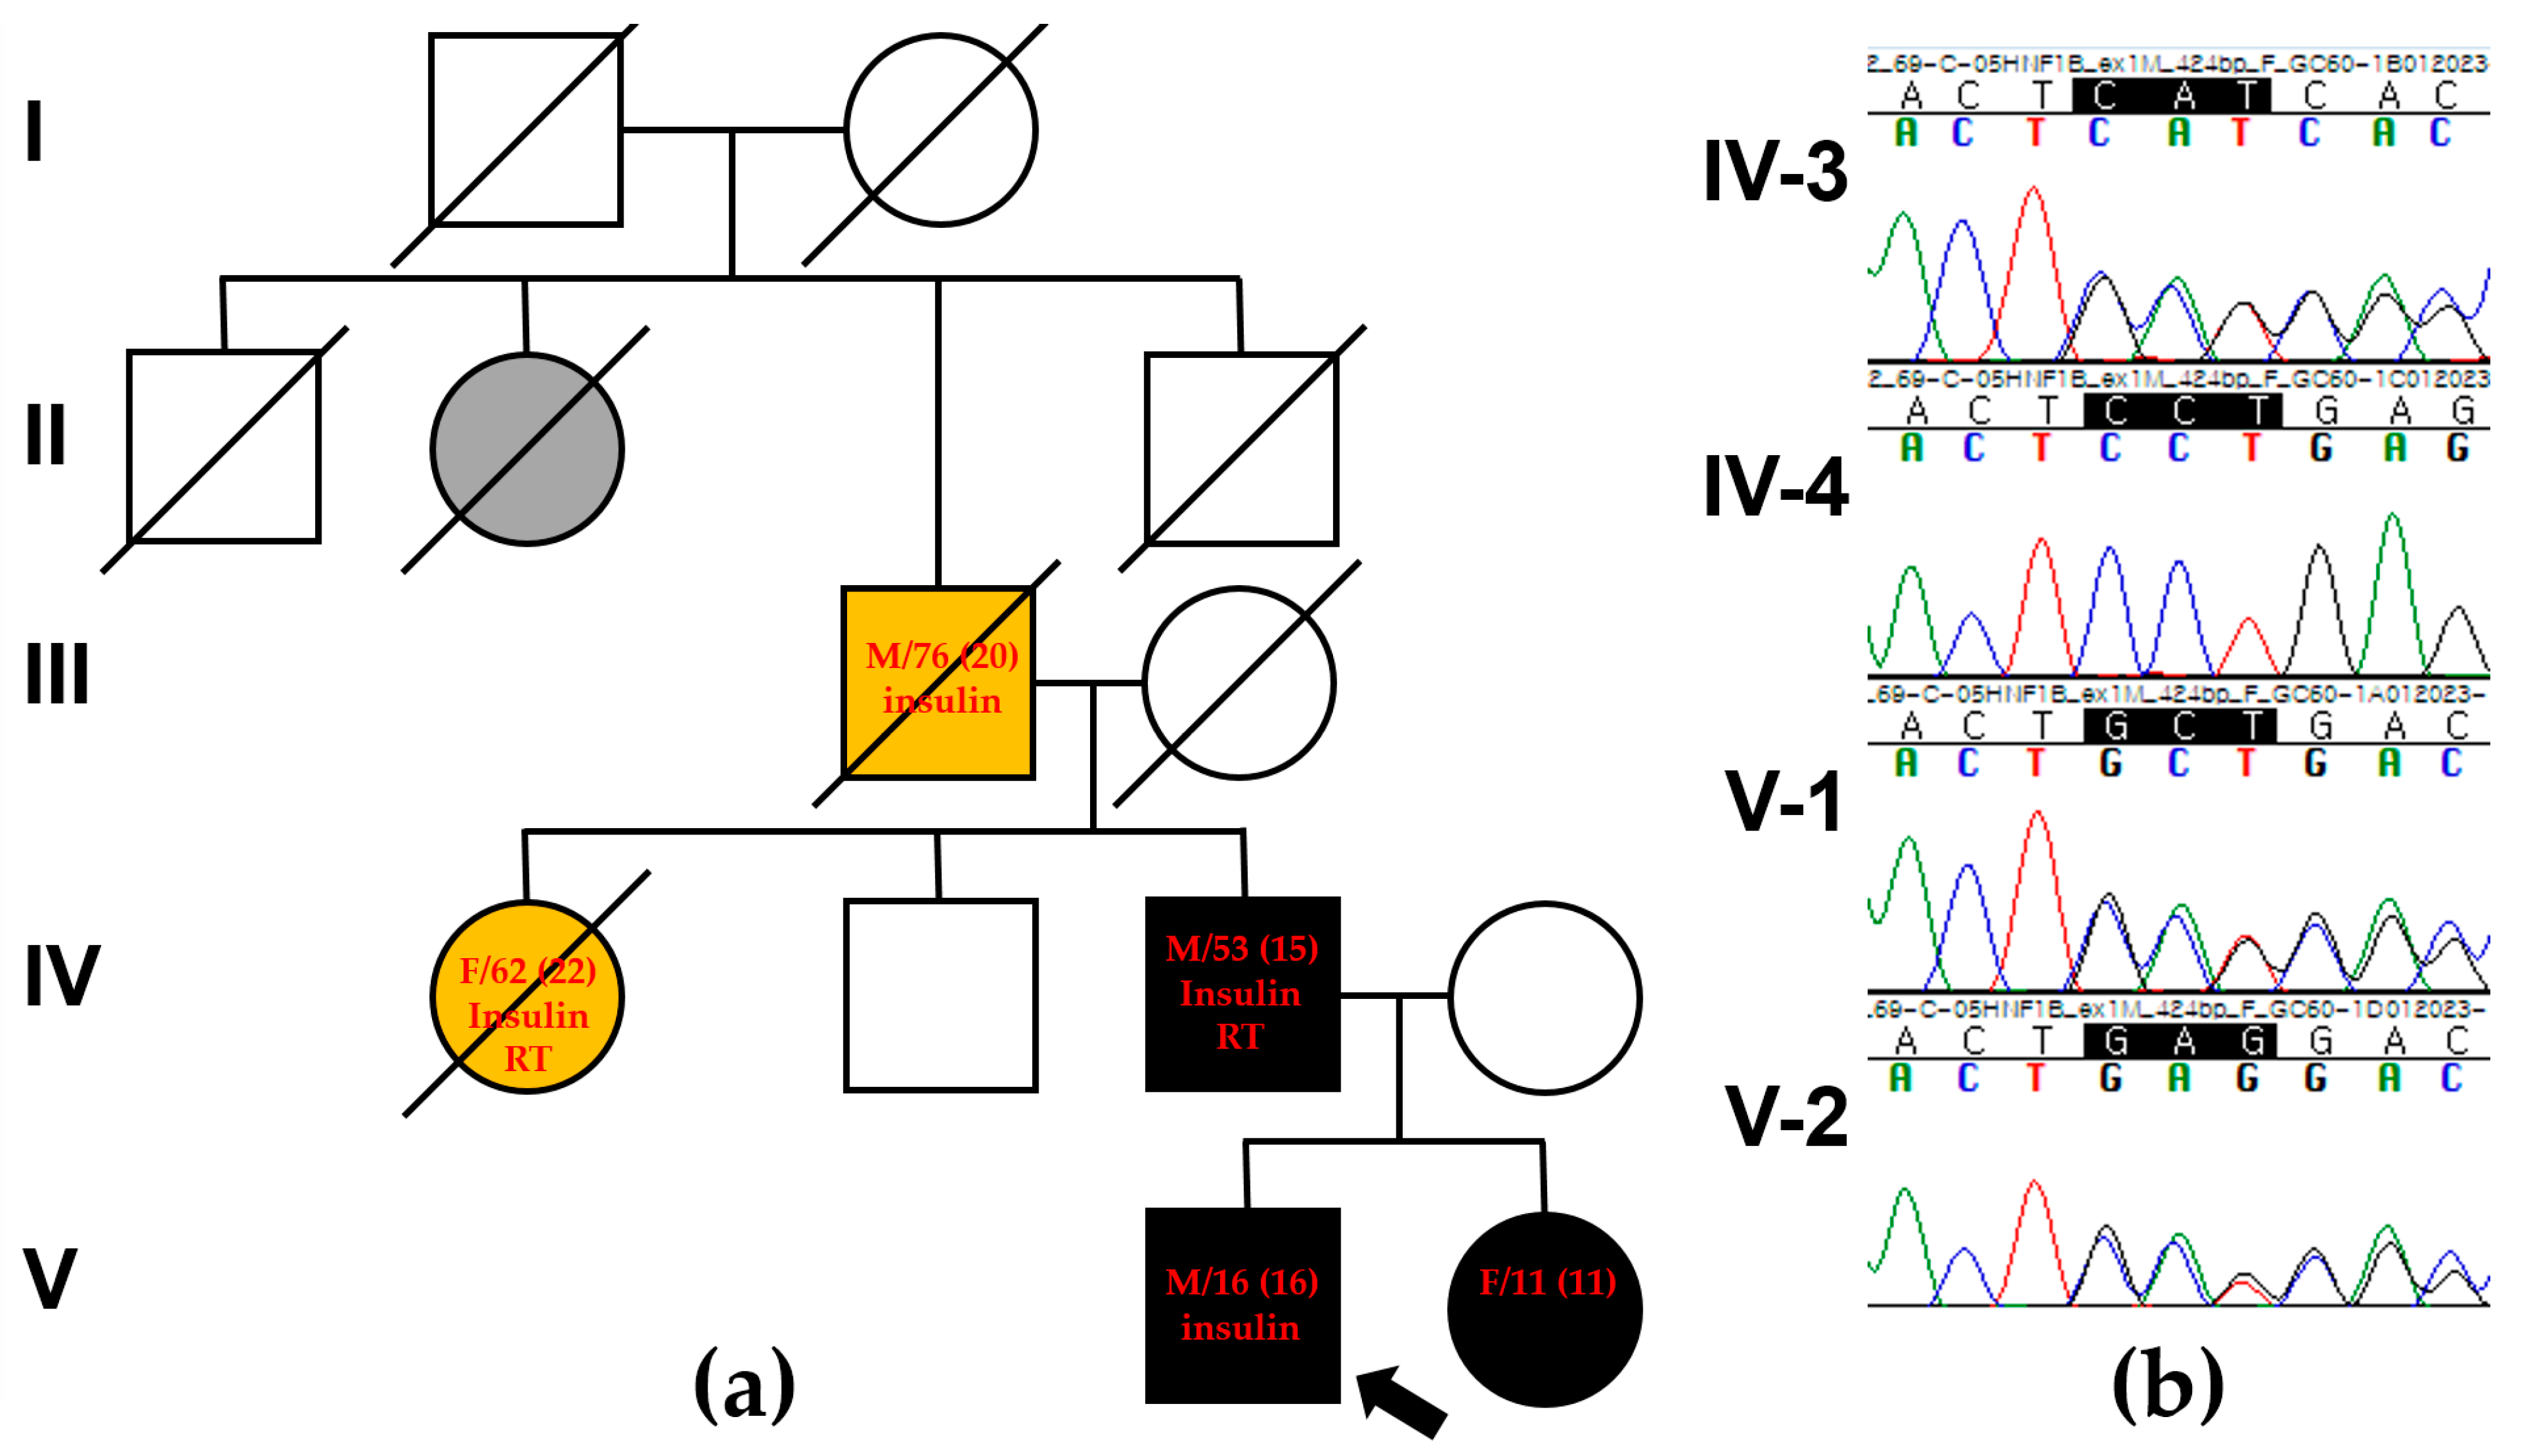

2. Case Presentation

3. Genetic Testing